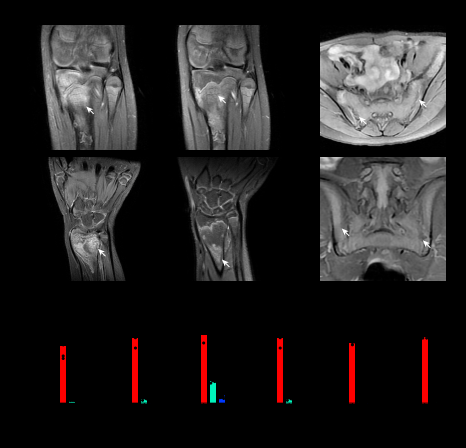

研究人员检测了思思的基因突变位点并进行了一系列体外实验研究

接受卡那单抗治疗后的思思各项检测均趋于正常